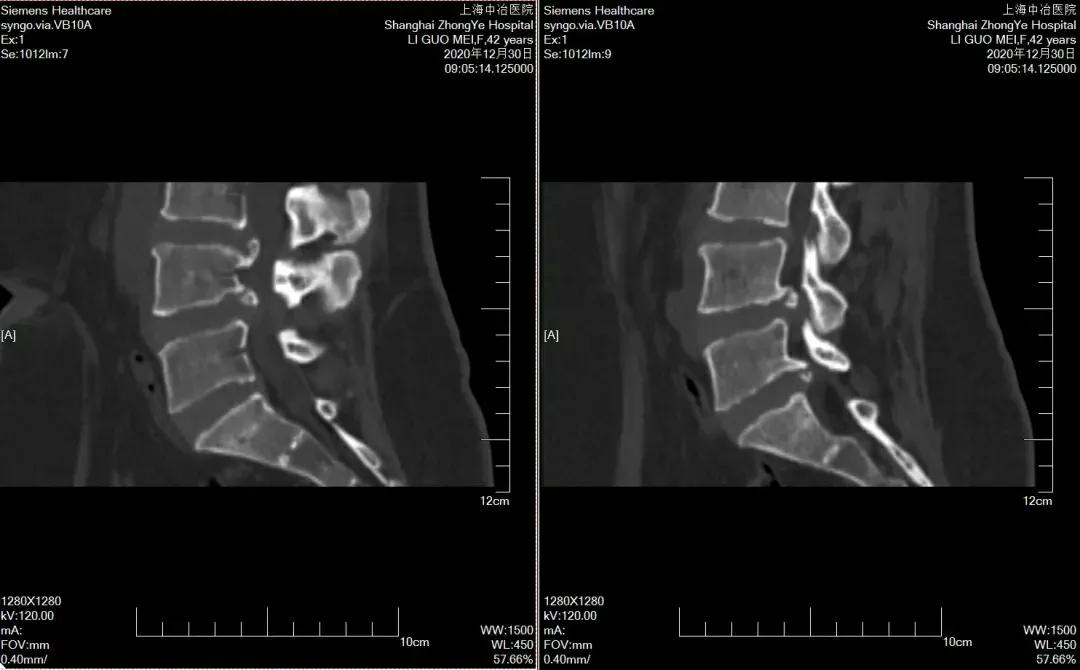

CT

可显示骨性椎管形态,黄韧带是否增厚,椎间盘突出的大小及方向,是否伴有钙化等。

核磁共振MRI

可全面观察各腰椎间盘是否病变,椎管内是否存在占位性病变,黄韧带是否增厚,椎管是否狭窄,较CT显示更加清晰。